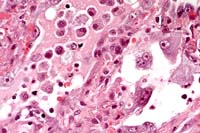

40x

Obj.

- Case 4-4. Lung. There is proliferation of type II

pneumocytes. Alveoli are filled with macrophages, fewer lymphocytes

and edema and occasionally contain syncytia. Alveolar septae

are thickened by fibrin, histiocytes and large pneumocytes.

- AFIP Diagnosis: Lung: Pneumonia, bronchointerstitial,

necrotizing, acute to subacute, diffuse, with alveolar edema,

few syncytial cells, and numerous amphophilic and eosinophilic

intranuclear inclusions, leopard cat (Felis bengalensis), feline.